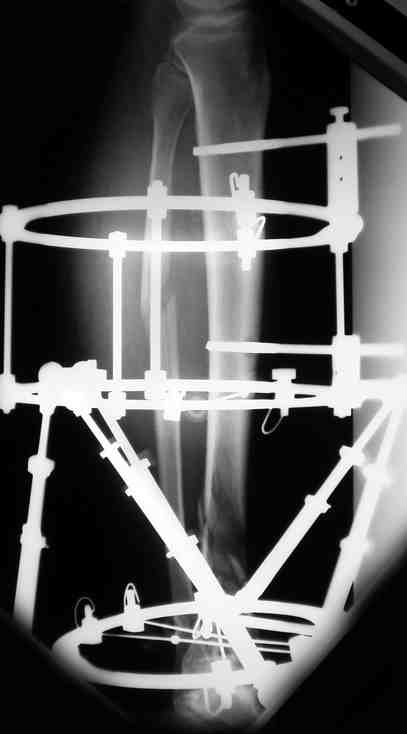

Выше представлены рентгенограммы открытого оскольчатого перелома нижней трети голени X-rays of Compound Comminuted # Distal/3 Lt Tibia

Операционные снимки перед и после наложения аппарата Илизарова In operation room before and after Ilizarov apparatus has been applied

Послеоперационные рентгенограммы Postoperative X-rays

В нижнем ряду представлены рентгенограммы после окончательной репозиции. And final reduction after Hexapod program has been finished